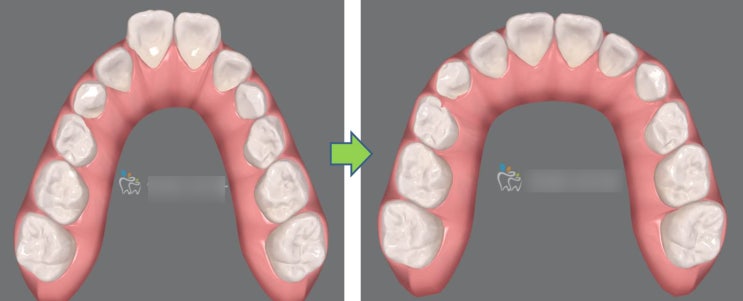

영구치(선천적 결손) 없는 과개교합 케이스 안녕하세요 교정전문의 최혜영 원장입니다. 오늘은 아래 작은어...